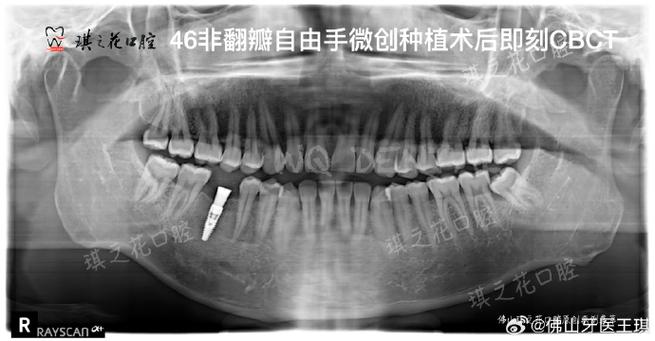

而CT(口腔种植常用锥形束CT,简称CBCT)能生成三维立体图像,可精确测量牙槽骨的骨高度(如种植区距离上颌窦底、下颌神经管的距离)、骨宽度(是否足够容纳种植体直径)、骨密度(骨密度过低会影响种植体骨结合),若上颌后牙区牙槽骨高度不足5mm,种植体可能穿入上颌窦,引发感染或种植体失败;若下颌骨宽度不足5mm,植入种植体时可能损伤下牙槽神经,导致下唇麻木,CT能清晰显示这些关键数据,帮助医生判断是否需要植骨、骨增量,或选择更短的种植体,避免盲目手术。

- 即刻种植/即刻负重可行性评估:若患者符合即刻种植条件(如拔牙后牙槽骨无明显吸收、无急性炎症),CT能评估拔牙窝的骨量和形态,判断是否可即刻植入种植体,甚至结合临时修复体实现“当天种牙、当天戴牙”,缩短治疗周期。